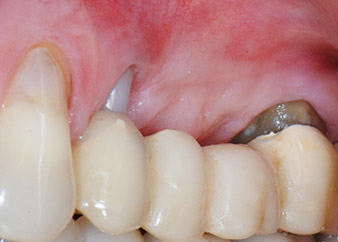

Figures 17 and 18 show the clinical result two months after the surgery. Tooth 24 exhibited reduced mobility of Miller class 1, and the soft tissues were free of inflammation. Probing was avoided at this point of time to prevent reinfection and to avoid violating the epithelial attachment. A control visit was scheduled for reentry and placement of healing abutments, six months after the insertion of the implants.

Two months after the surgery, the patient was pain-free.

Fig. 17: Two months after the surgery, the patient was pain-free and the area was free of inflammation.

after the surgery

Fig. 18: Tooth 24 now showed less mobility.

At the two-months recall, the mobility of the remaining “dental element” 24 was already reduced from Miller 2 to Miller 1. The soft tissue attachment was on the level of the neighbouring tooth 23. Moreover, there were no endodontic or periodontal symptoms, so its prognosis may have to be readjusted.

However, as most of the buccal and proximal bone is missing and the composite build-up extends to the apical section of the root, a higher reattachment level is not to be expected due to biologic reasons (Sculean et al., 2008).